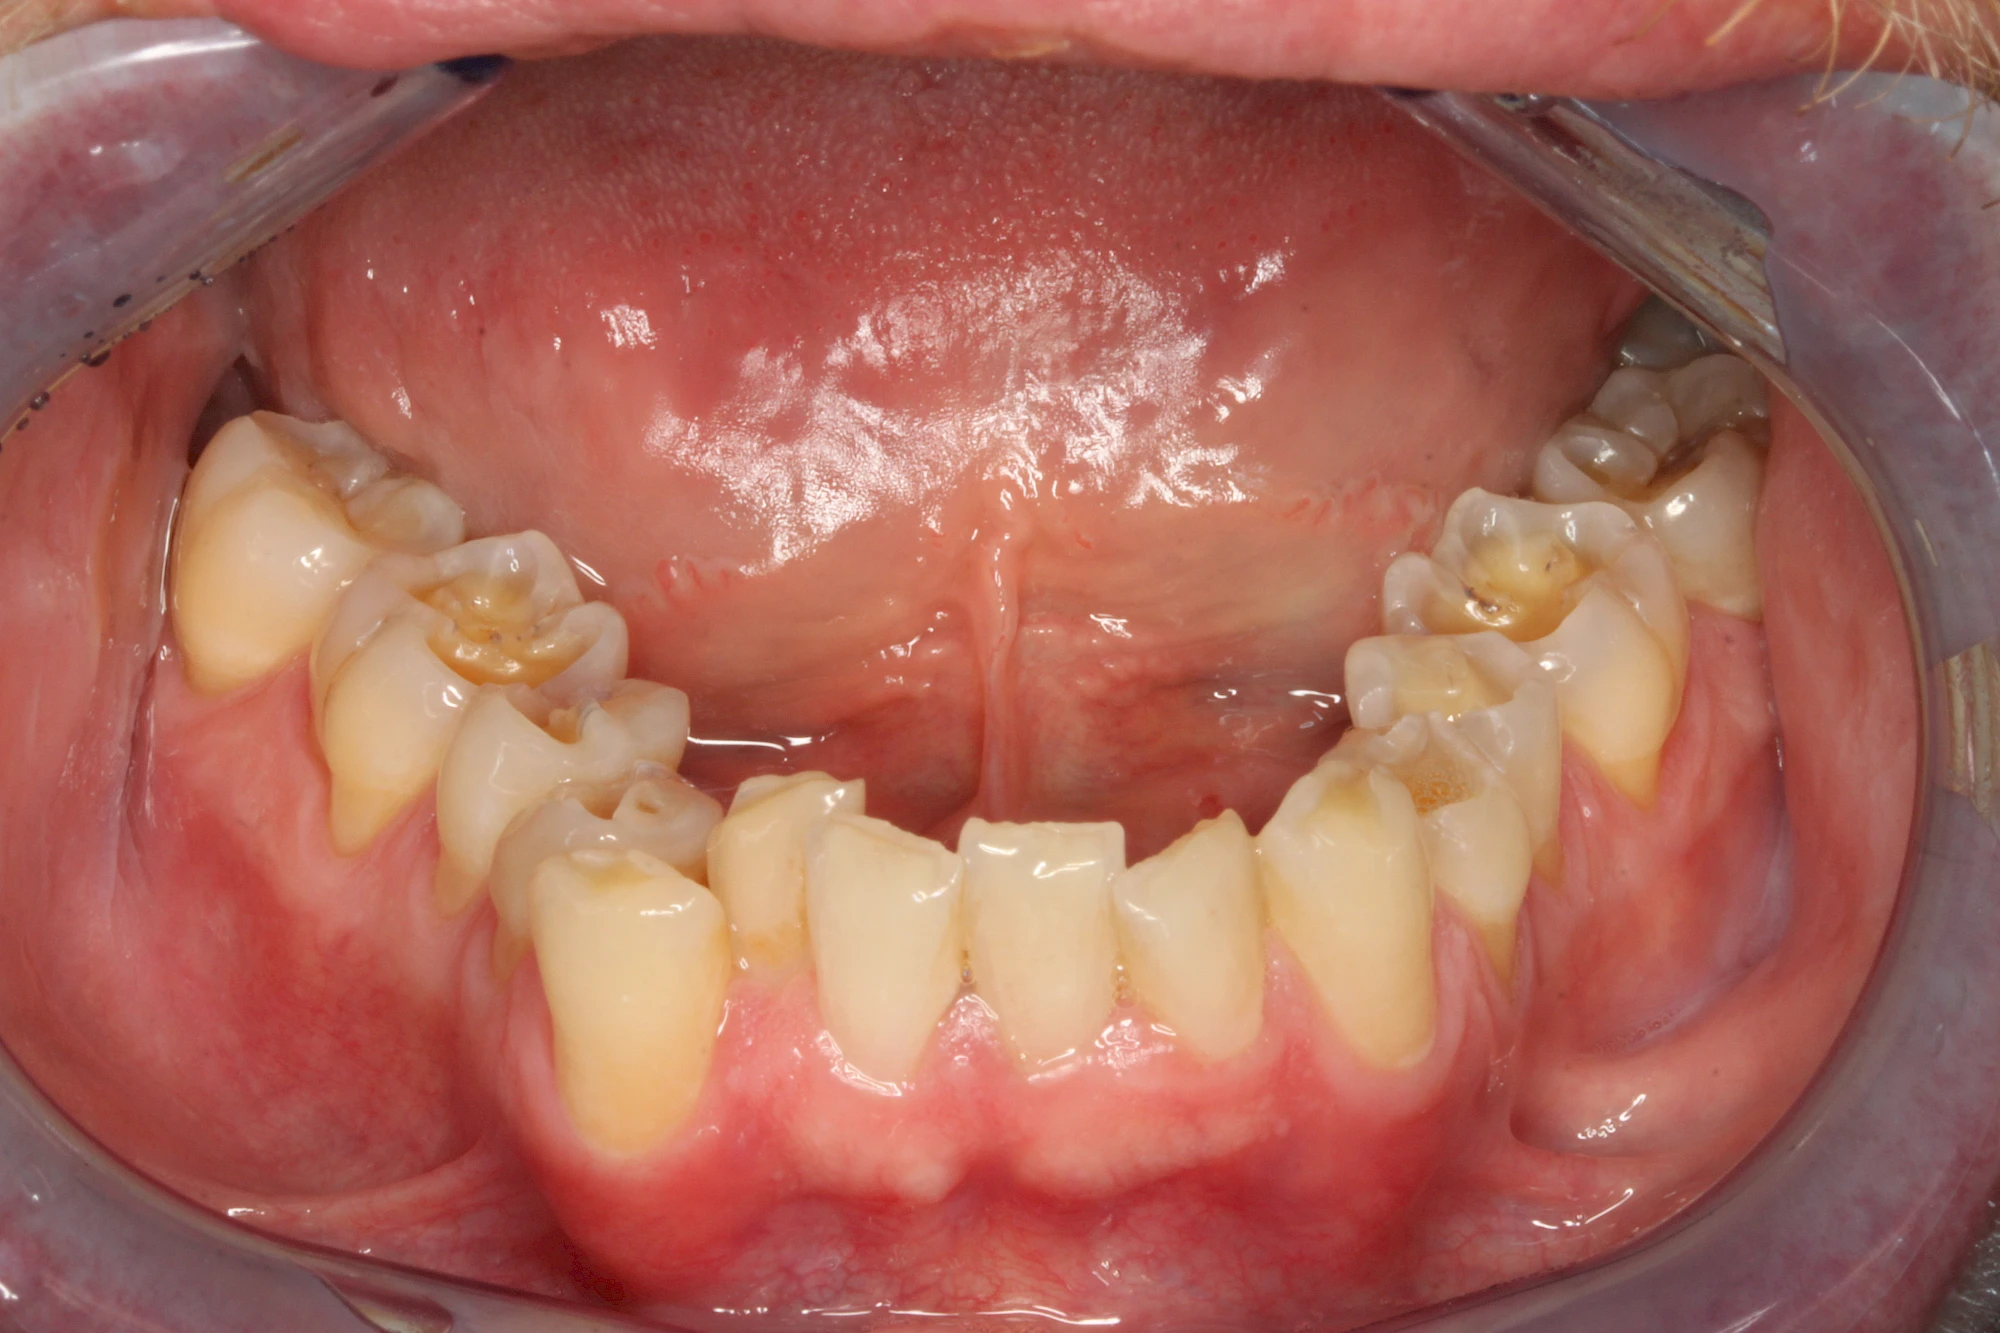

- Abnutzung durch Kauen (Abrasion) oder duch durch übermäßiges Knirschen bzw. Pressen (Attrition)

Auswaschung (Erosion) dagegen ist eine Verschleißerscheinung der Zähne aufgrund von immer wiederkehrenden Säureangriffen durch die Nahrung, verstärkt zum Beispiel durch den Genuss säurehaltiger Getränke oder Speisen. Auch bei Menschen mit einer Essstörung (z. B. Bulimie) können die Zähne durch die Magensäure ausgewaschen erscheinen.